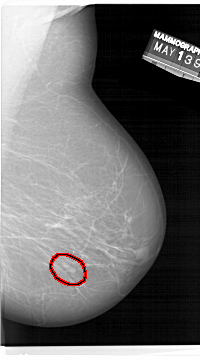

A_1471_1.LEFT_MLO

FILE: A_1471_1.RIGHT_MLO.OVERLAY

TOTAL_ABNORMALITIES 1

ABNORMALITY 1

LESION_TYPE MASS SHAPE LOBULATED MARGINS CIRCUMSCRIBED

ASSESSMENT 4

SUBTLETY 4

PATHOLOGY BENIGN